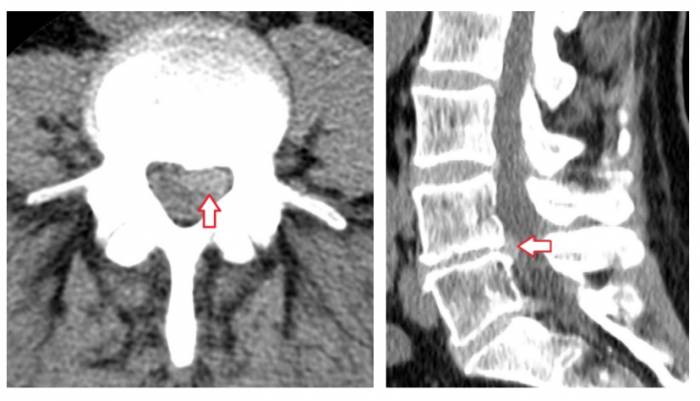

Грыжи межпозвонковых дисков при КТ позвоночникаклассифицируются в зависимости от их локализации. Так, выделяют задние, латеральные и передние грыжи дисков — в зависимости от того, в какую сторону выпадает межпозвонковый диск. Задние грыжи в свою очередь могут быть центральными (диск выбухает кзади по средней линии), медиаолатеральными (диск выбухает в латеральный карман справа либо слева), фораминальными (диск выбухает в межпозвонковый канал). Грыжа диска может быть также внутрикостной (по типу т. н. грыжи Шморля) — при этом происходит пролабированиепульпозного ядра в тело позвонка с проламыванием его замыкательной пластинки.Грыжа Шморля при компьютерной томографии позвоночника выглядит как дефект тела позвонка, отграниченный плотным склерозированным «ободком». Редко встречается также вариант интрадурального пролапса (грыжи), когда секвестр распространяется под твердую оболочку спинного мозга.

Пример парамедианной грыжи межпозвонкового диска в пояснично-крестцовом сегменте позвоночника при компьютерной томографии (грыжа диска отмечена стрелкой). В диске визуализируются также включения газа («вакуум-фемонен»), отмечены красной звездочкой «*».

Пример медиолатеральной грыжи МПД в сегменте L4-L5, распространяющейся в латеральный канал. Грыжа диска при КТ визуализируется в виде гиперденсного объекта (край диска выбухает по дуге малого радиуса) в левую сторону, вызывая сдавление нервного корешка и выраженный болевой синдром.